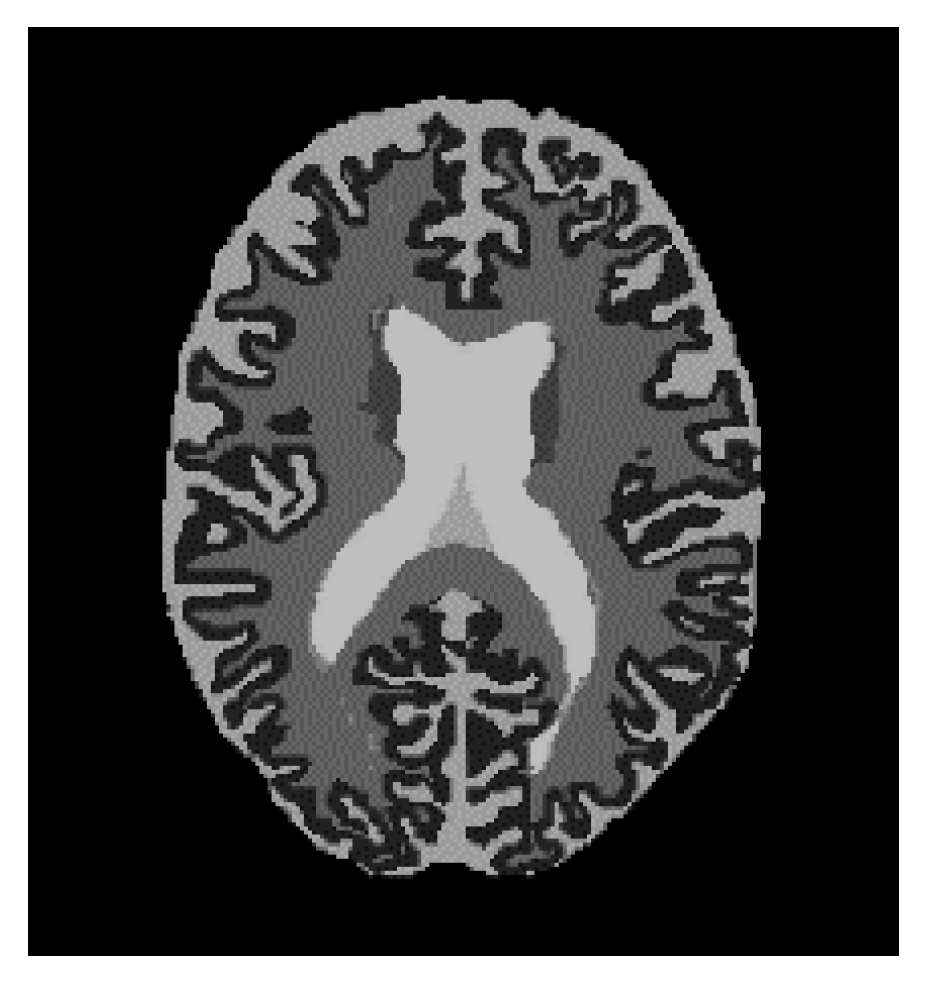

3.1. Border Enhancement Network

5.1. Border Enhancement Experiment